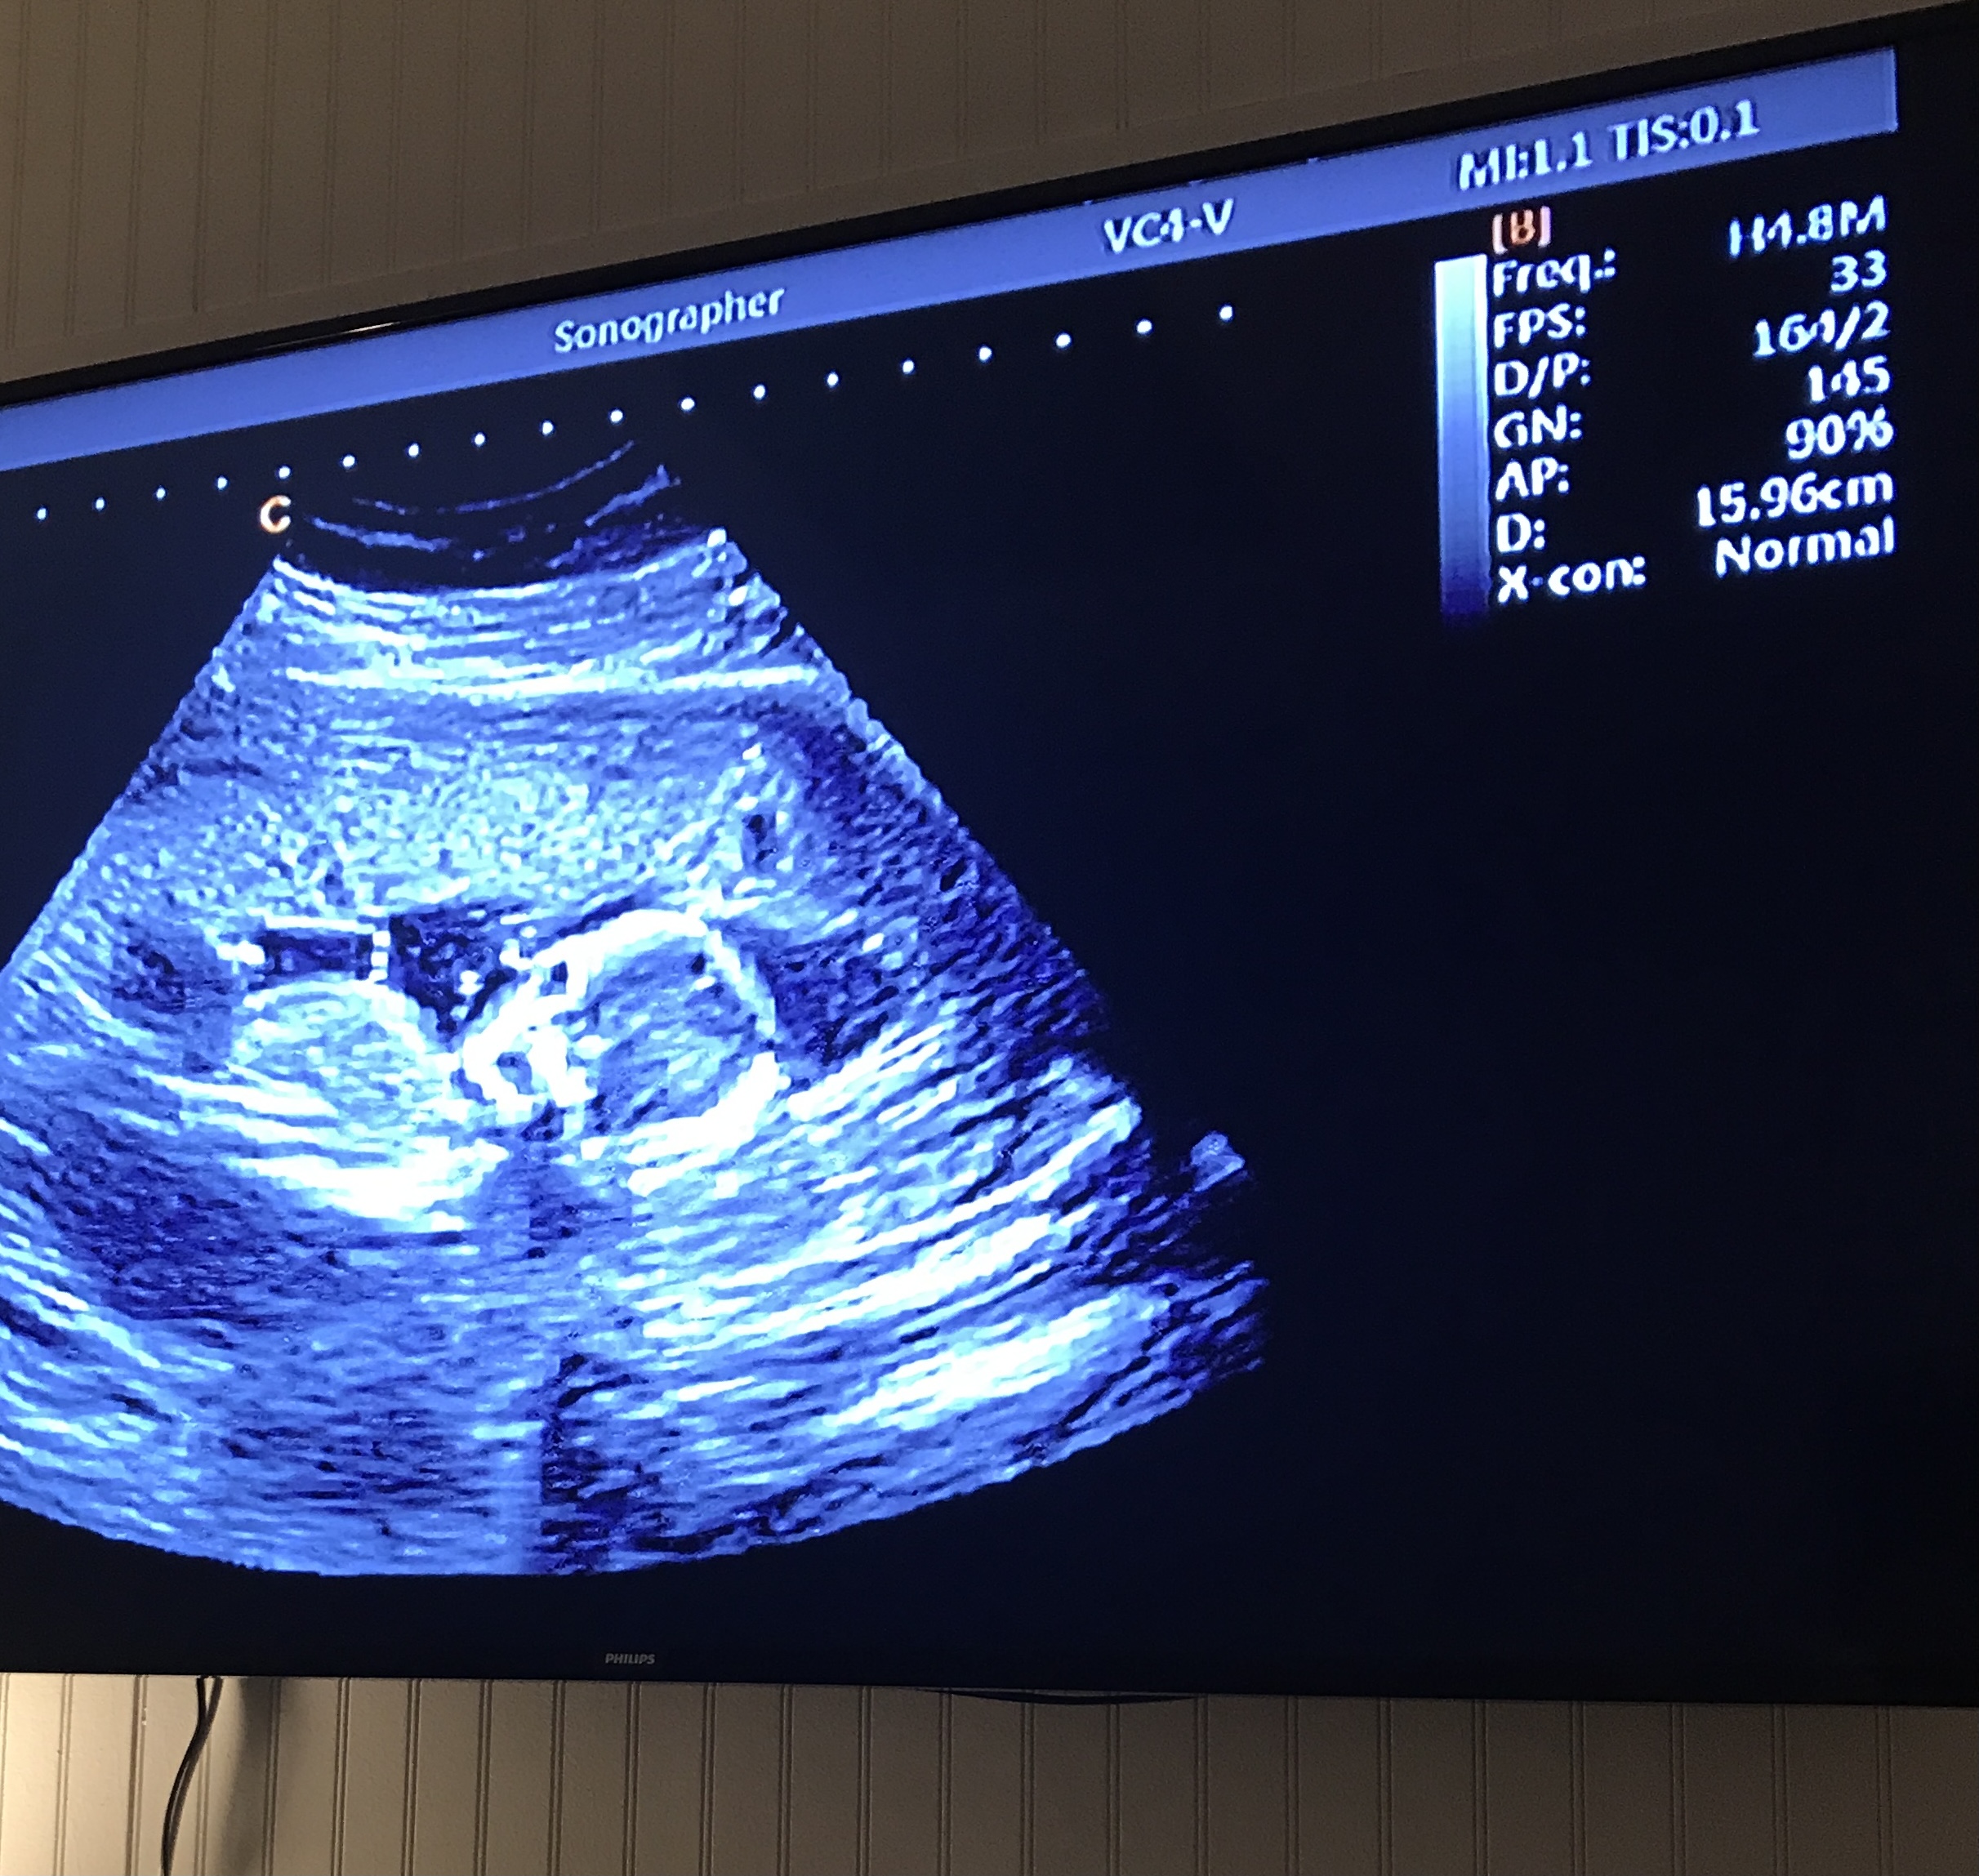

Gates performs the ultrasounds in a large, comfortable room that can accommodate about 15 people. Images, or video, of the baby are shown in real time on a large screen television.

The 4D ultrasound imaging is the most unique service offered at First Glance. During a 4D ultrasound a live video is created with movie like quality to capture the baby’s facial expressions.